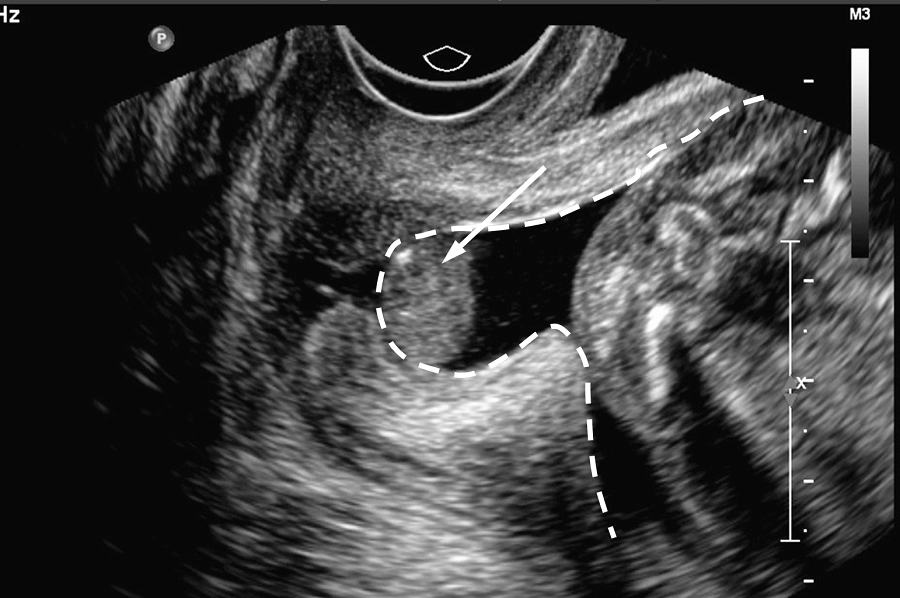

婚後懷孕15周無徵兆流產,第一次月經乾淨後做了宮頸內口探察,最先開始是找醫生開單,列印檢查專案單,然後去進行繳費,我是下午一點做手術的,在手術時門口更換好衣物,將醫療手冊交給護士,醫生用鴨嘴夾撐開然後用探棒進行檢查,發現宮頸口很鬆,告知我下次懷孕14周後要做宮頸環扎術,之後開了消炎藥就回家了,如果有需要做宮頸檢查的姐妹可以通過我的經歷看看檢查的流程。宮頸內口探察經歷準備工作流產後來一次月經,乾淨後...

初次懷孕22周突然流血,保胎2周還是失敗,檢查後發現我宮頸機能不全,由於打擊太大過了一年我再嘗試備孕,懷孕後到蘇州附二院檢查,醫生沒有讓我做環扎手術,但我每2周還是要做一次供精檢查,後面宮頸還是開了,於是住院保胎,不打針吃藥,一直躺到了36周,出院後發現內口又閉合了,40+3時,催產針一天,生下了我的寶貝,和我有一樣情況的姐妹也不必擔心,勇敢面對、積極保胎一定能夠順利生下健康寶寶。我的孕育心酸史第...